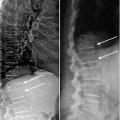

Scoliose dorsale droite

SCOLIOSE